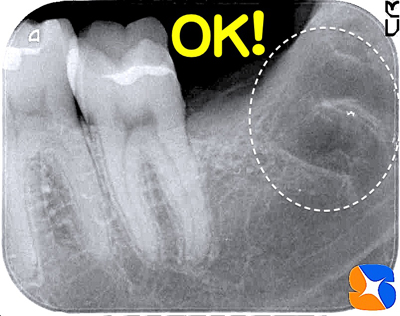

レントゲン写真の結果、親知らずの歯は、下のアゴ骨に真横に埋まっていました。更に根の先はカーブを描き、骨をホールドしています。難しい抜歯になると予測されたので、CT撮影を行いスムーズな抜歯を目指しました。

順調に抜歯を進めていたが、最終段階になって「バッキッ!」と嫌な音。直ぐにレントゲンで確認すると、2本の根の先が、両方とも折れた状態で骨の中に取り残されていました。